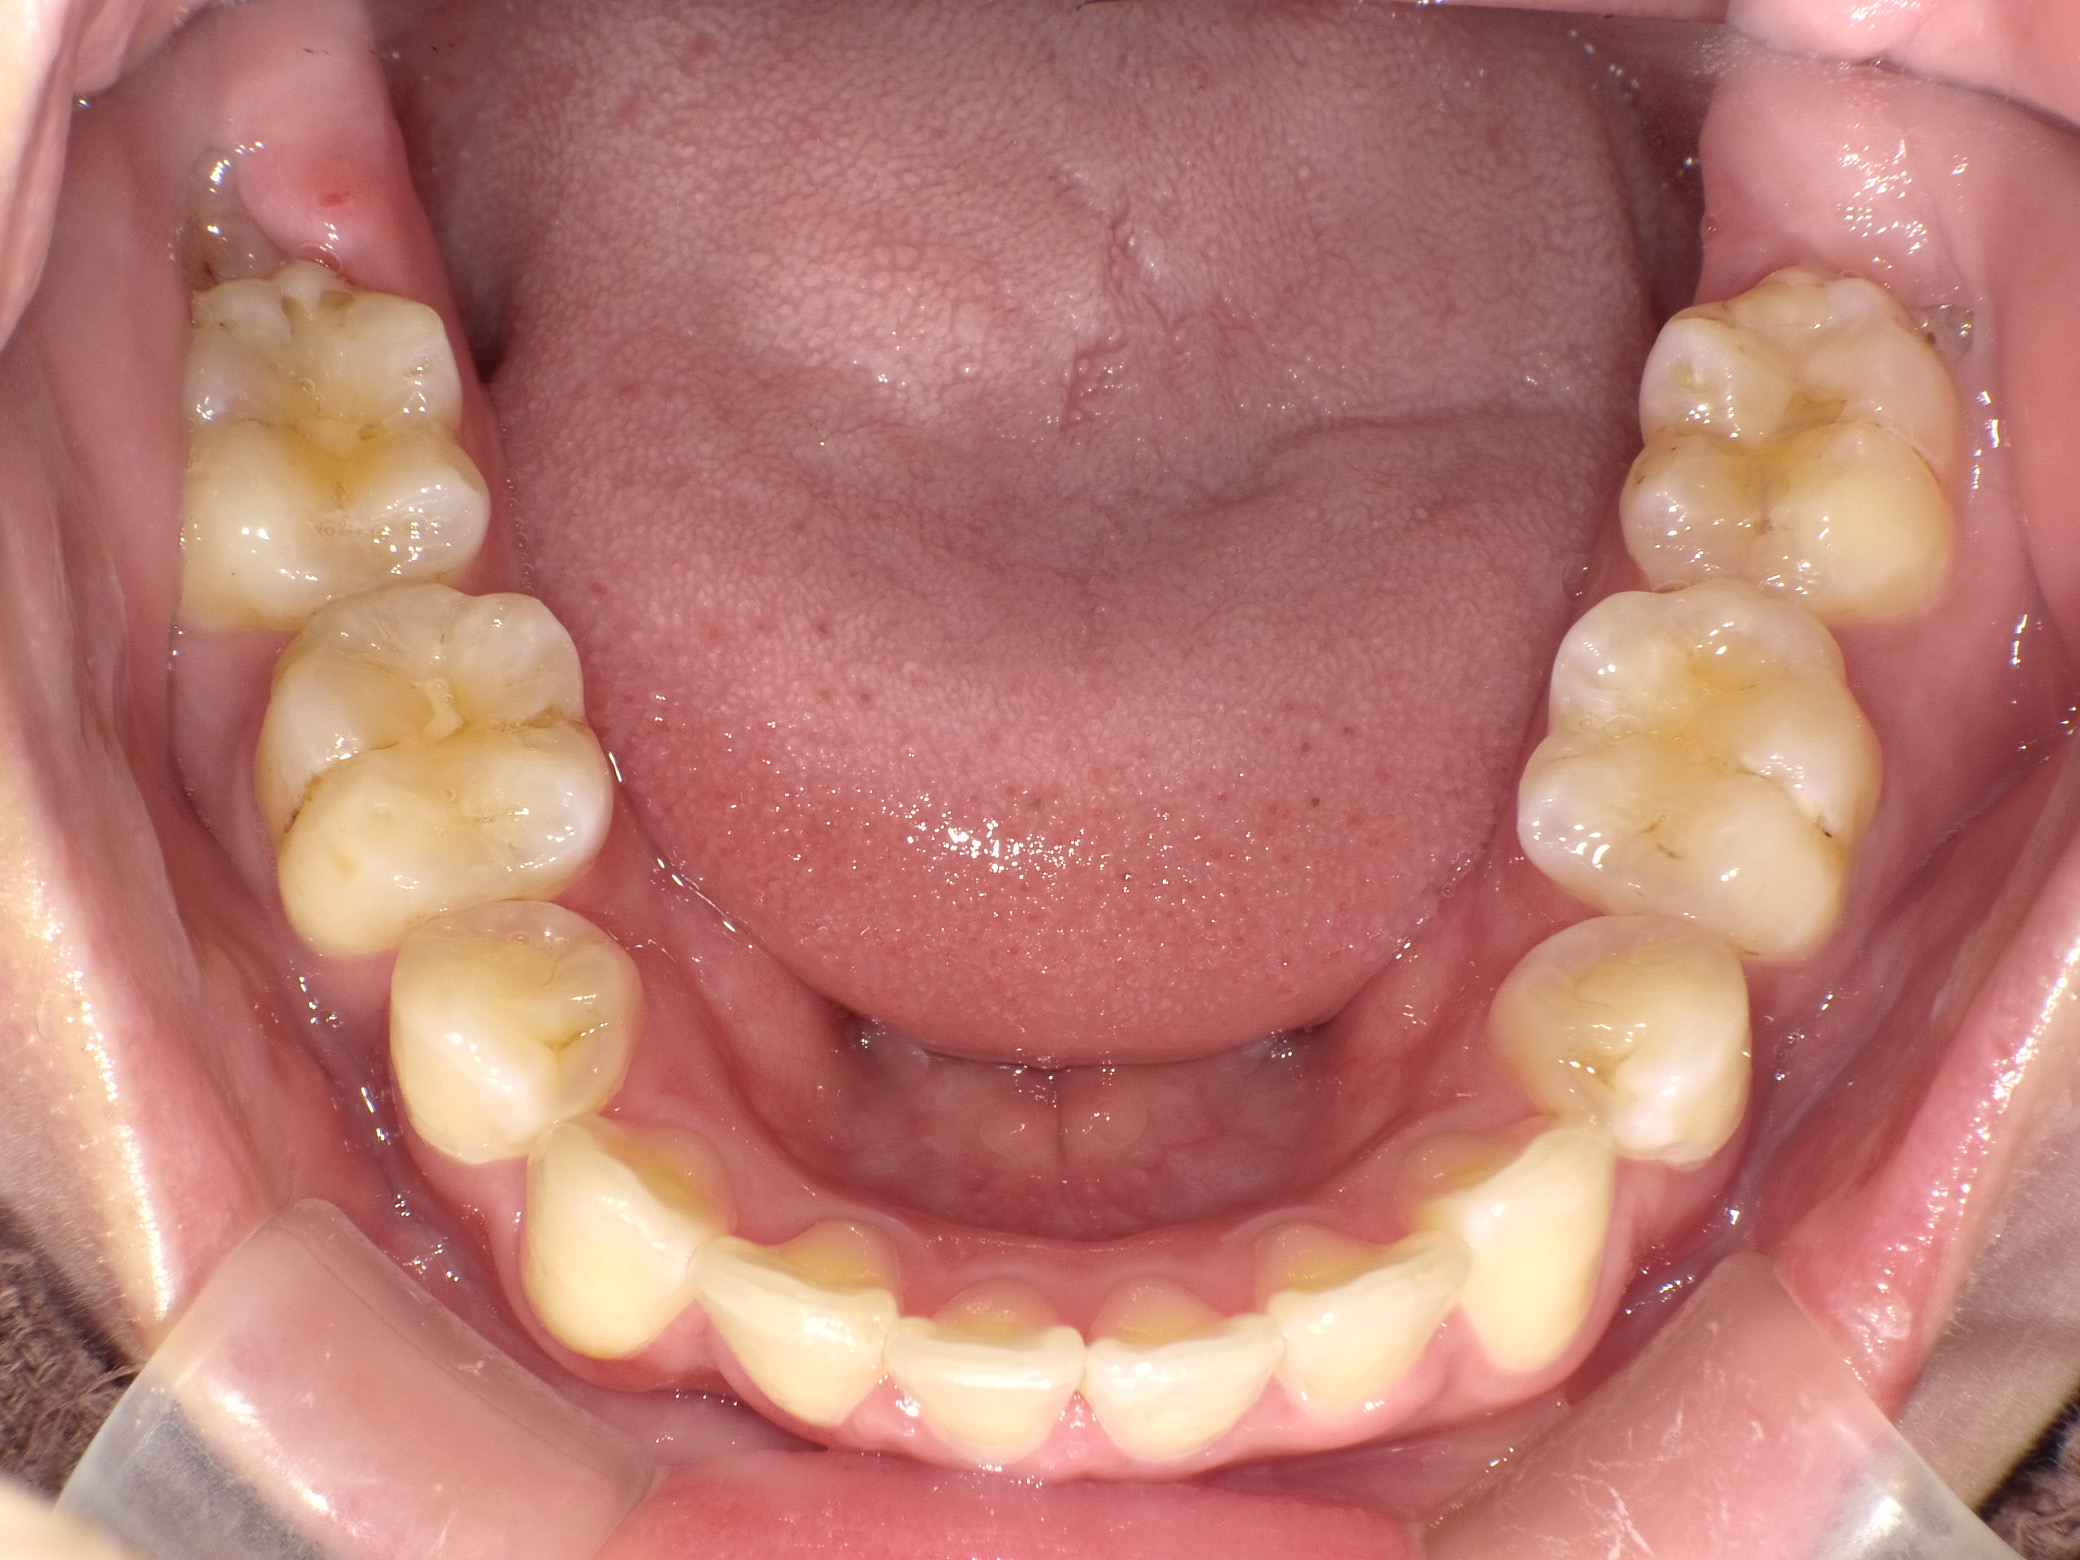

症例④

症例4_治療前 症例4_治療後

年齢・性別 24才男性

治療方法 ホワイトブラケット

治療期間 3年

治療総額 850,000円

特記事項 抜歯あり

リスク・副作用 治療の初期段階では痛みや不快感が生じやすくなりますが、1週間前後で慣れます